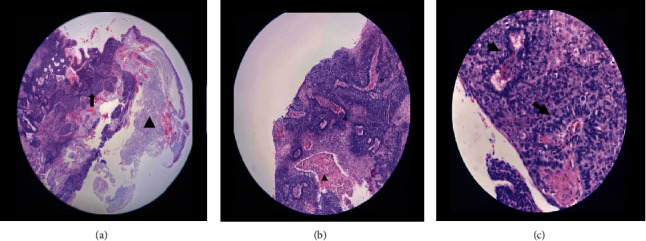

Objective: To describe the morphological and histopathological features of primary conjunctival basal cell carcinoma (BCC) in a young adult Filipino. Introduction: Malignant conjunctival tumors arise from different cells, the most common of which are squamous cell carcinomas (SCCs), (including ocular surface squamous neoplasia [OSSN]), melanomas, and lymphomas. Primary conjunctival BCC is rare and can mimic the clinical features of OSSN. Only seven reported cases were published. Most cases are in the 6th-8th decades of life, and we report the first case in a young adult male. Case Summary: A 37/M, HIV-seronegative, presenting with a 3-year history of enlarging fleshy, pedunculated mass on the right eye measuring 8.5 mm × 8.0 mm at the superonasal limbus encroaching on the cornea, with prominent feeder vessels. Whitish-to-grayish plaques were observed on the surface of the lesions. Wide excision of the mass using the no-touch technique was performed under local anesthesia. Four cycles of mitomycin C (0.02%) were administered as chemoadjuvant therapy. Histopathology showed basaloid cells with peripheral palisading, most consistent with BCC. Immunohistochemistry was positive for Bcl-2 and CD10 markers and negative for epithelial membrane antigen (EMA) and carcinoembryonic antigen (CEA), confirming conjunctival BCC. Eight weeks postoperatively, fibrovascular tissue proliferation was noted at the excision site. Anterior segment-optical coherence tomography (AS-OCT) revealed a thickened hyperreflective band that was continuous with the epithelium, indicating possible recurrence. Resection with rush frozen section revealed fibrotic tissue that was negative for tumor cells. The bare sclera was covered with conjunctival autograft. There was no recurrence of the lesion after 16 months of follow-up. Conclusion: Primary BCC of the conjunctiva is rarely encountered, especially in young individuals, mimicking squamous neoplasia both in morphology and histopathology. Therefore, this should be considered in the differential diagnosis of OSSN. Immunostaining is crucial in differentiating between the two conditions and confirming the diagnosis. In most cases, wide surgical excision is sufficient. In addition, adjuvant therapies may be beneficial in preventing tumor recurrence.